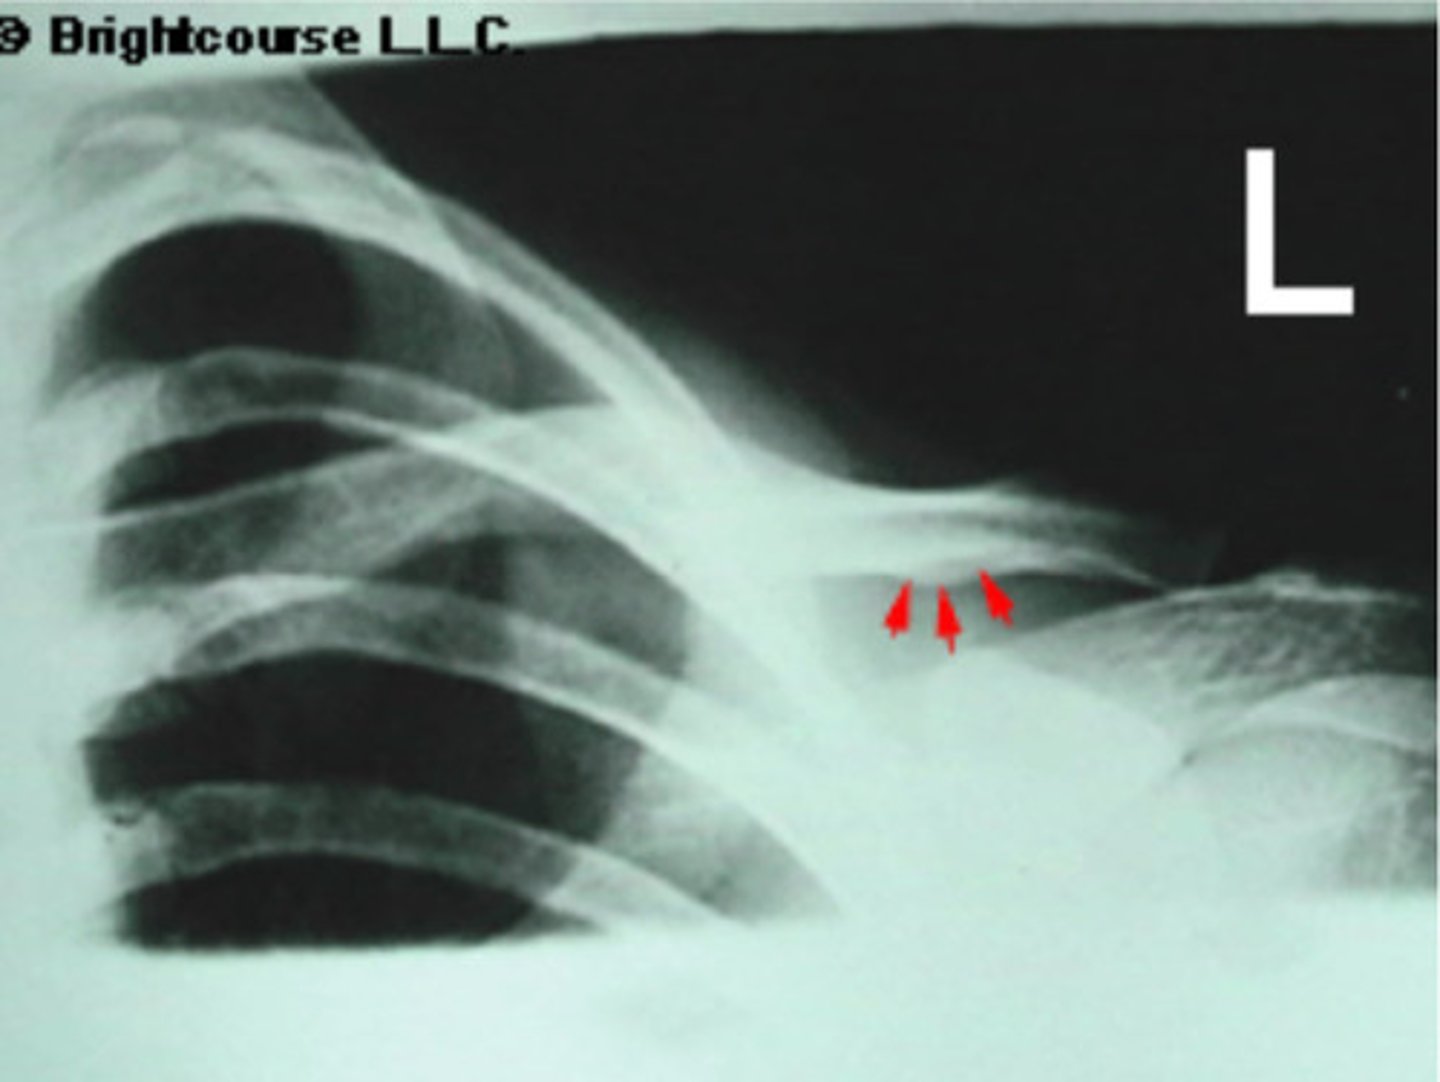

Soft tissue

What is being pointed out by the arrows in this image?